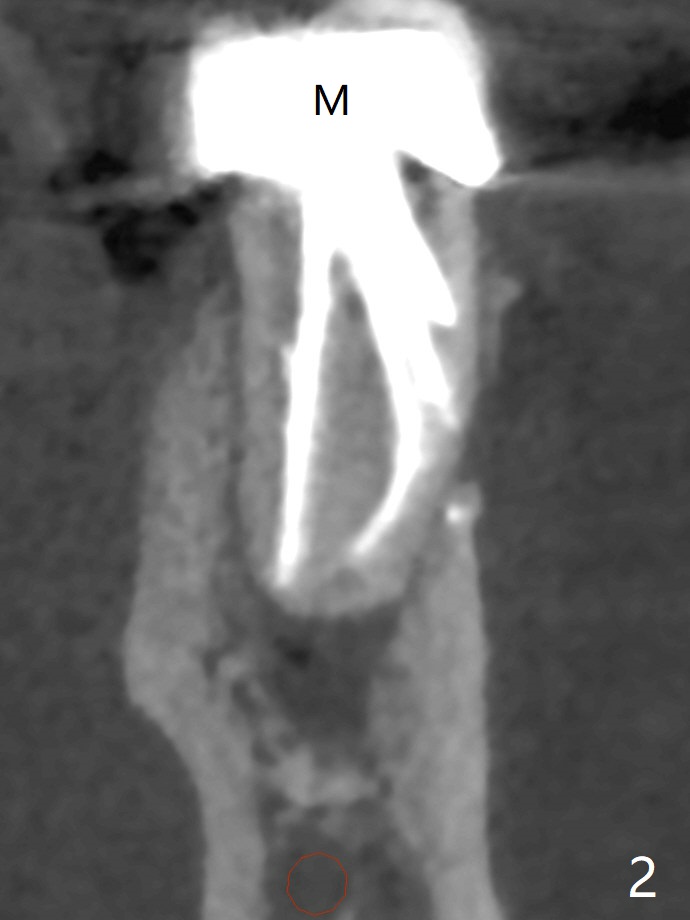

The tooth #19 of a 61-year-old man develops pain 9 years post complicated RCT (Fig.1). Periradicular radiolucency is more around the mesial root (Fig.2) than the distal one (Fig.3). Section the crown to check whether the distal margin is restorable. Remove the mesial root to determine whether the distal one is salvageable or not. If not, place a 5x15 mm bone-level implant with guide. To reduce the chance of screw loosening, consider placing a tissue-level implant (Fig.4,5). Preserve the buccal crestal bone (Fig.6 *) during extraction and debridement, which keeps the socket open for bone graft and healing. Draw blood for PRF PRN for membrane and sticky bone.